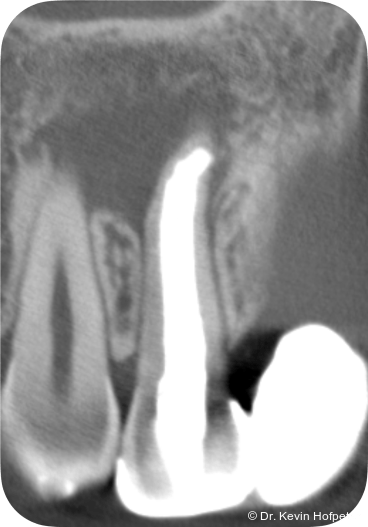

Zwei Monate später konnte die definitive Obturation erfolgen. Da der Kanal nun trocken war, konnte die Dentinbrücke im apikalen Bereich unter Sicht entfernt werden (Abb. 3). Das Mineral Trioxid Aggregat (MTA, Medcem) wurde frisch mit steriler Kochsalzlösung angemischt und mithilfe einer MTA-Gun (MAP-System, Produits Dentaires) sowie individuell angepassten Guttaperchastiften in den gekrümmten Kanalabschnitt eingebracht. Die größte technische Herausforderung bestand im Einbringen eines dichten apikalen MTA-Verschlusses hinter der Kurvatur (Abb. 4). Nachdem dieser Verschluss gesetzt war, wurde der restliche Kanal mit einem Epoxidharz-Sealer (AH Plus, Dentsply Sirona) und erwärmter Guttapercha mittels warm-vertikaler Kompaktion gefüllt und der Zugang adhäsiv verschlossen (Abb. 5).

Kontrollaufnahmen nach drei, sechs, neun, zwölf und 24 Monaten zeigten eine fortschreitende knöcherne Heilung (Abb. 6–10). Die Patientin war beschwerdefrei und zeigte sich mit dem Ergebnis sehr zufrieden. Radiologisch war eine deutliche Rückbildung der Läsion erkennbar, wenngleich eine geringe apikale Aufhellung persistierte. Weitere Verlaufskontrollen wurden empfohlen.